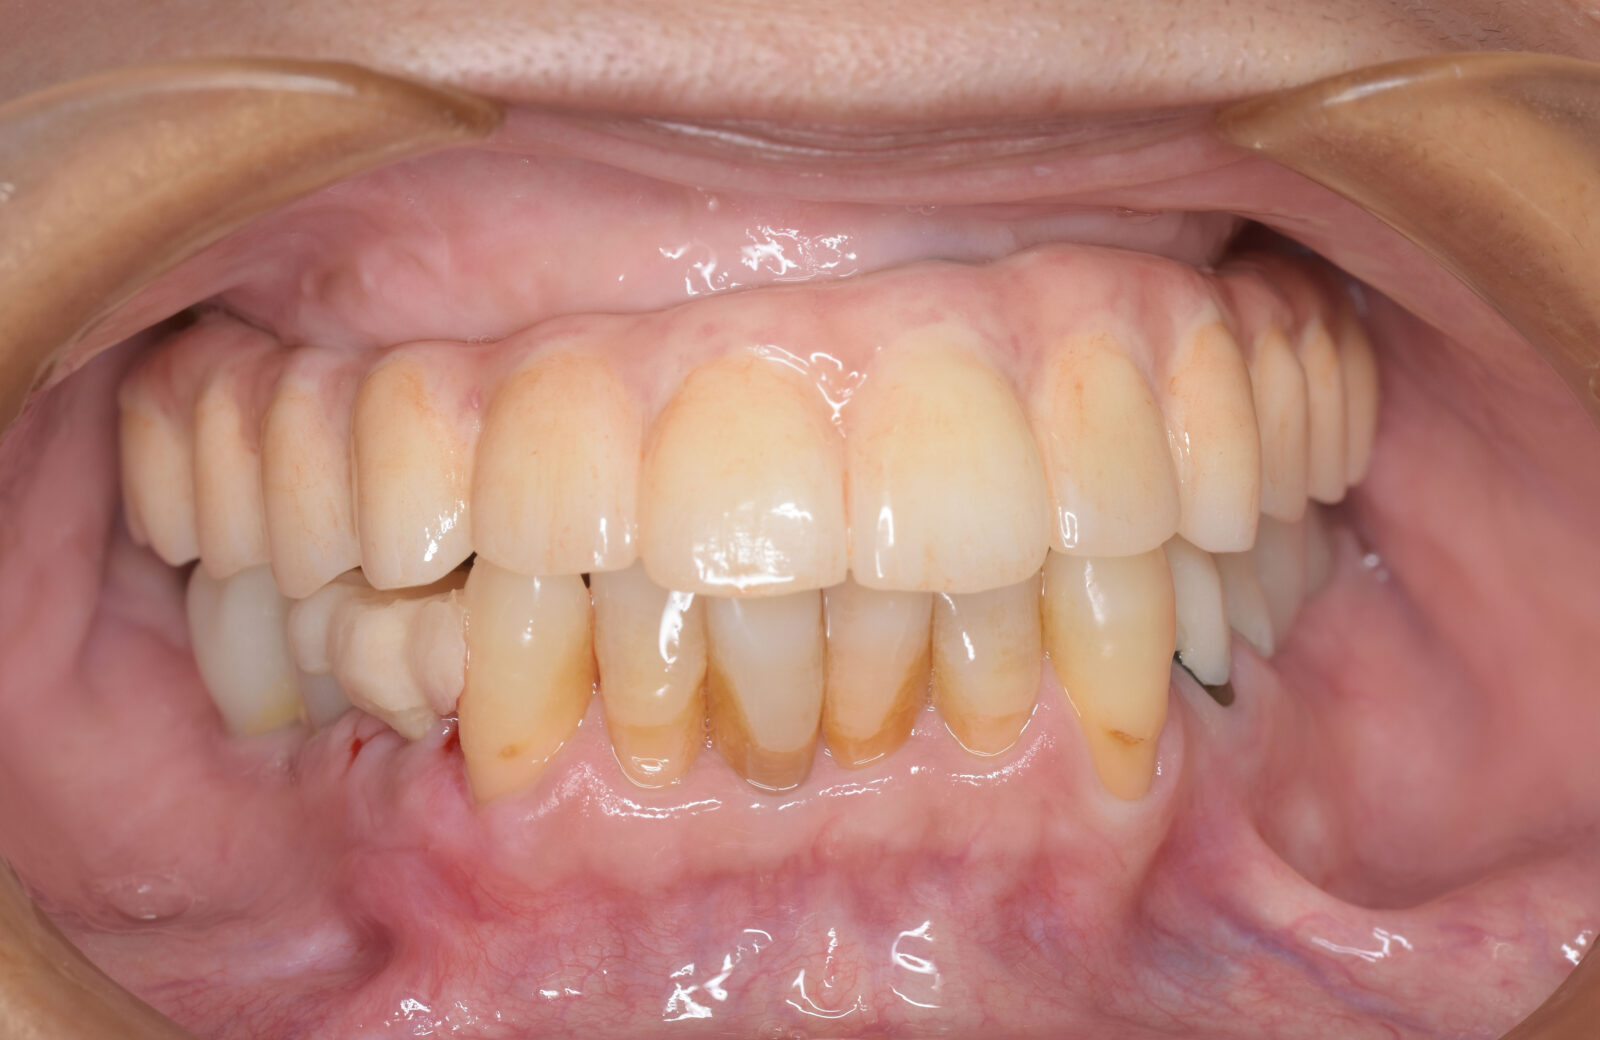

• 治療前

• 治療後